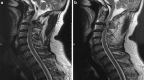

Methods: A 49-year-old Chinese male presented with a progressive cervical myelopathy (C-JOA score 11 immediately pre-op). Segmental OPLL at the C2-3 disk space was visible, together with invagination of the bilaterally hypoplastic C2 lamina into the spinal canal. Signal abnormalities of the spinal cord were evident on both T1 and T2 sequences.